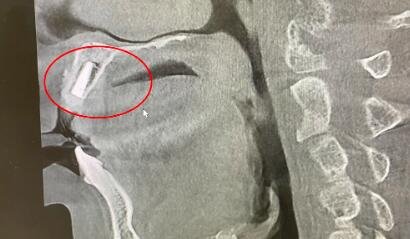

王师傅术后即刻复查X片,显示种植体种植到位

王师傅的种植牙第一期手术——种植体植入,用时仅30分钟,术后即刻复查X片显示种植体种植到位,初期稳定性好。王师傅对整个手术过程非常满意,预计3个月后,接受二期基台安装及牙冠修复。